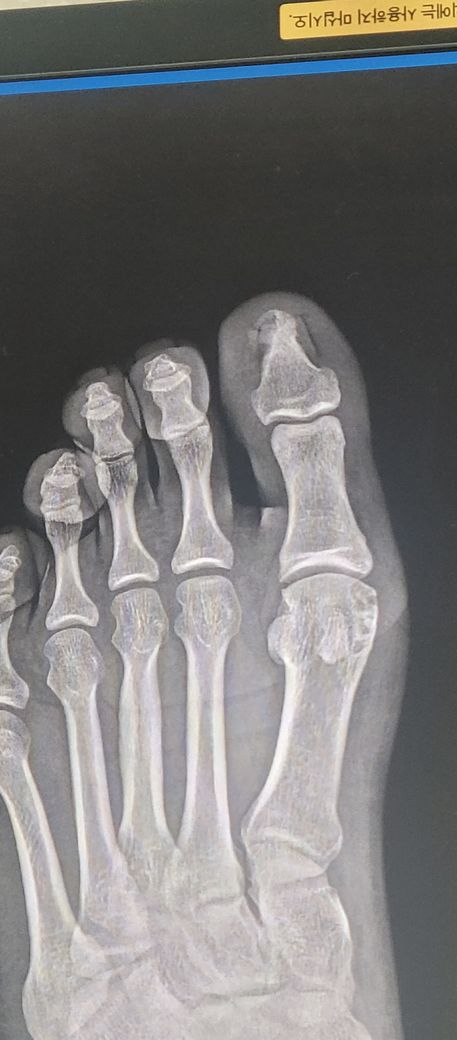

운동화 신고 에스컬레터 내려가는길 넘어져 엄지발가락 옆 뼈를 부디쳤는데 뛸때 마다 통증이 있어요 뼈가 구멍이난거처럼 그렇기에 피검사 후 요산 수치가 7.93 입니다 통풍이맞나요? 아님 단순 통증인가요? 한번도 아픈적 없었습니다.

엄지발가락을 부딪힌 후 통증이 있다면 타박상이나 미세골절 가능성이 있습니다 요산 수치가 7.93으로 다소 높은 편이지만 통풍은 외상없이 갑자기 발생하는 심한 통증이 특징이라 이번 통증과 직접적인 연관은 낮아보입니다 통증이 지속되거나 부기가 있다면 정형외과에서 엑스레이 검사를 받아보는 것이 좋아요!

질문자분께서 올려주신 영상자료에서도 특이한 것은 보이지 않는 것 같구요, 다만 요산수치는 성인 남성의 경우 7이하로 유지되는 것이 좋으니 이점은 지속적으로 관리하시는 것을 추천드립니다.